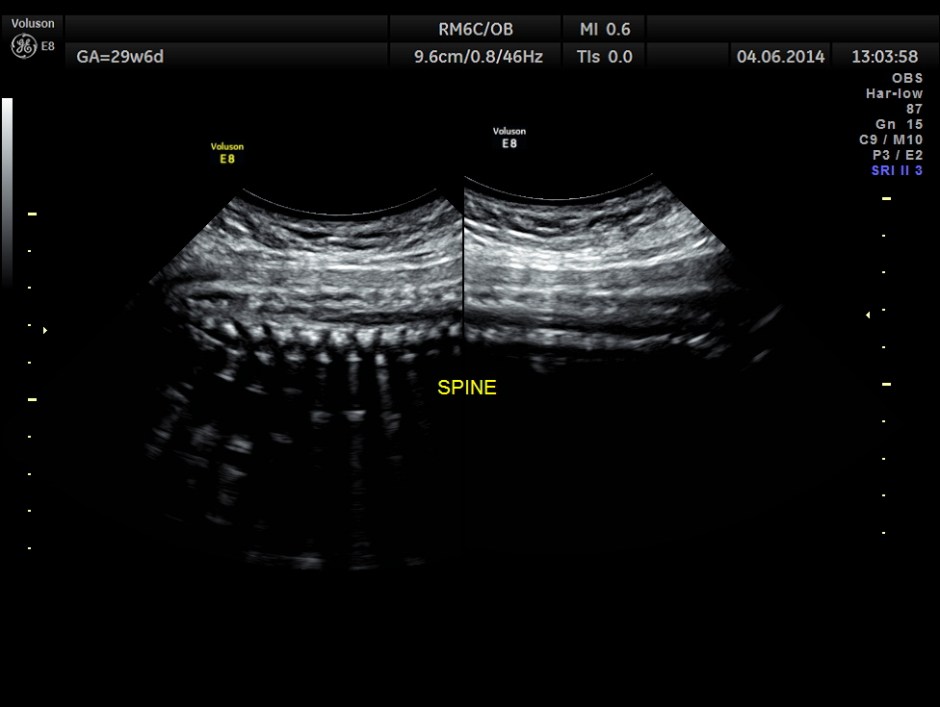

She had a thick placenta , but appears homogenous.